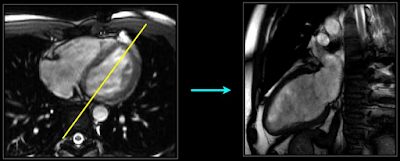

In a 4Ch view, all 4 chambers of the heart are visible and in the 2Ch view, only two are visible. To create the 4Ch view, the radiographer first prescribes a line on the transverse image, and then on the 4Ch view image, he/she prescribes another line passing through the left side of the heart (through the mitral valve and ventricular apex), slicing the image to create the 2Ch view. The workflow below shows the 4Ch view on the left and how a line is drawn (shown in yellow) to slice the image and create the 2Ch view on the right.